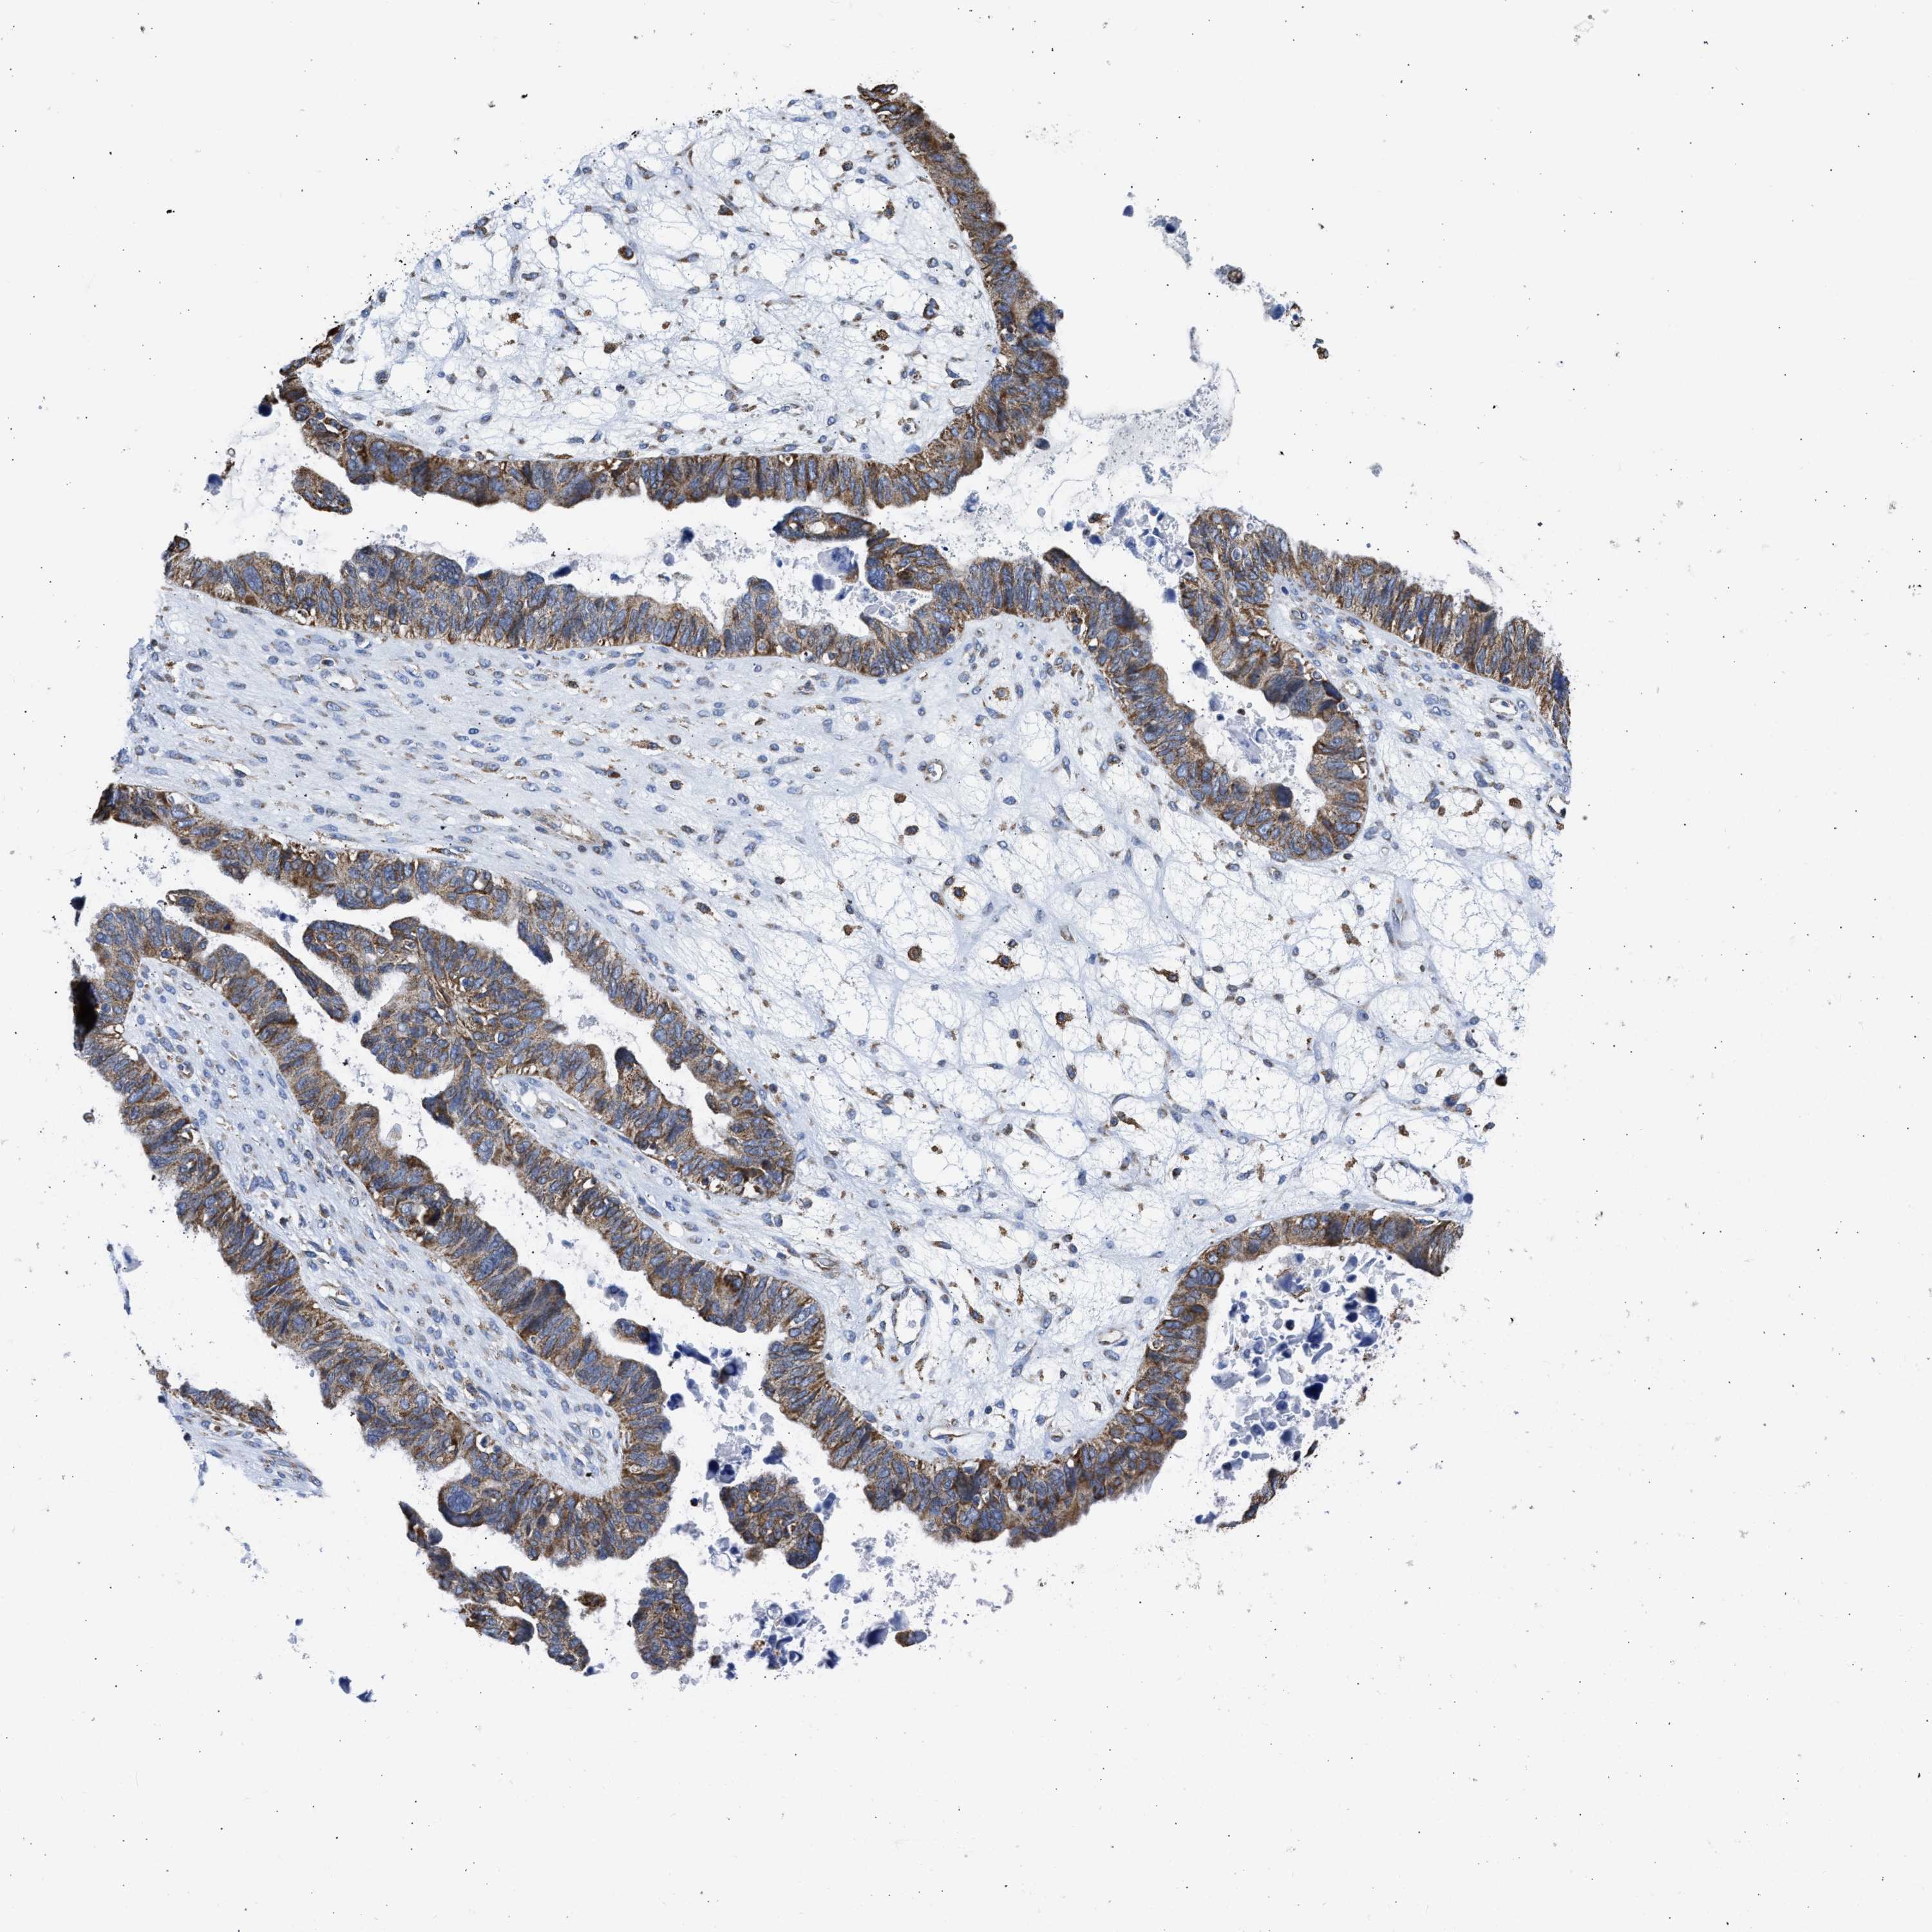

OVARIAN CANCER - Protein expressioni

A mouse-over function shows sample information and annotation data. Click on an image to view it in a full screen mode. Samples can be filtered based on level of antibody staining by selecting one or several of the following categories: high, medium, low and not detected. The assay and annotation is described here.

Note that samples used for immunohistochemistry by the Human Protein Atlas do not correspond to samples in the TCGA dataset.

Antibody stainingi

Antibody staining in the annotated cell types in the current human tissue is reported as not detected, low, medium, or high, based on conventional immunohistochemistry profiling in selected tissues. This score is based on the combination of the staining intensity and fraction of stained cells.

Each image is clickable and will lead to virtual microscopy that enables deeper exploration of all samples and also displays staining intensity scores, fraction scores and subcellular localization as well as patient and tissue information for each sample.

Antibody CAB004222

Antibody CAB005126

Antibody CAB018597

Cystadenocarcinoma, serous, NOS

Cystadenocarcinoma, mucinous, NOS

Carcinoma, endometroid

Carcinoma, NOS